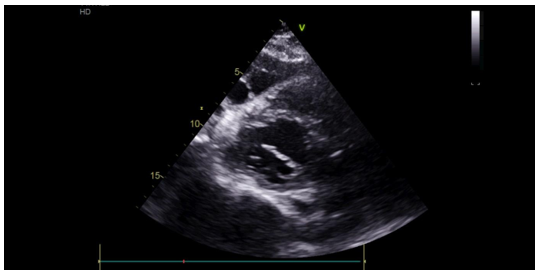

The transthoracic echocardiographic examination revealed (Figures 8 – 18):

- A lobulatedcystic image exerting severe compression on both the right and left cardiac chambers, resulting in hemodynamic disturbance and considerable fluctuation in respiratory flows (Figures 12 – 13,17).

- Left ventricule showed no sign of dilatation. Al though the assessment of contractile function was influeced by compressio from pulmonary hydatid cyst, it appears to maintain functionnality.

- Elevated left ventricular filling pressure were noted.

- The right ventricle exhibited no dilation (Figure 11) despite the presence of longitudinal systolicdys functio n (Figures 14).

- Grade II tricuspid insufficiency was identified, with an estimated systolic pulmonary arterial pressure of 47 mmHg (calculated as 37 + 10 mmHg), indicating the presence of pulmonary hypertension.

- The inferior vena cavademonstrated no dilation (Figure 18) and wasnoted to be non-compliant (Figure 16).

- No pericardial effusion was present.